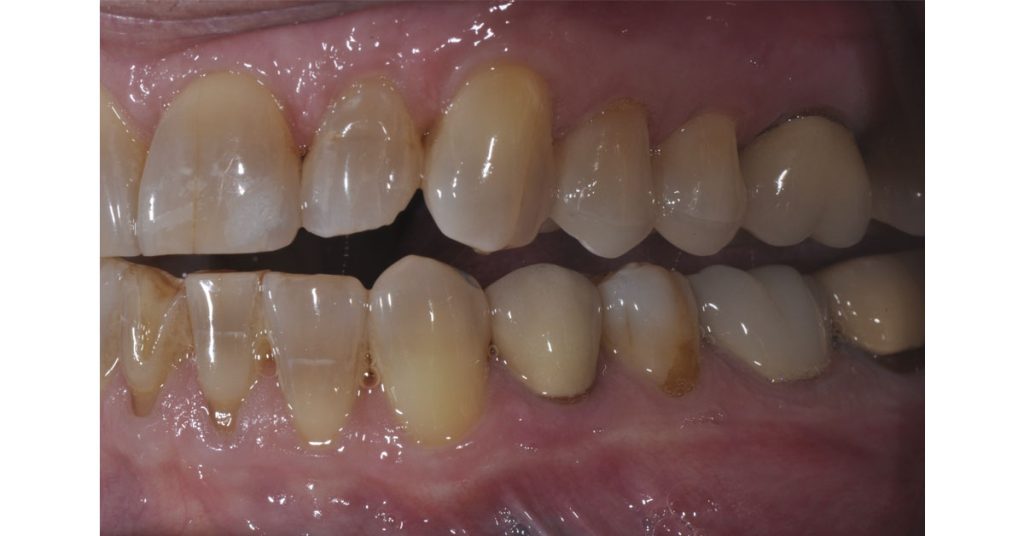

Long-term predictability may be achieved by incorporating proper planning and design into the posterior partial coverage ceramic restorations. This patient had significant erosion due to gastroesophageal reflux disease.

He had lost cuspal height and contour. The full-contour e.max ceramic onlays were fabricated with adequate thickness and ideal anatomy using the diagnostic wax-up as a guide for outcome-based tooth preparation. These restorations have now been functional for more than five years.

The following photos show the final ceramic onlays for the patient’s #12 and #13 teeth:

The “ideal reduction sauce” for these cases is to provide adequate space for anatomic contour and material strength. Proper planning and execution create predictable and long-lasting results.